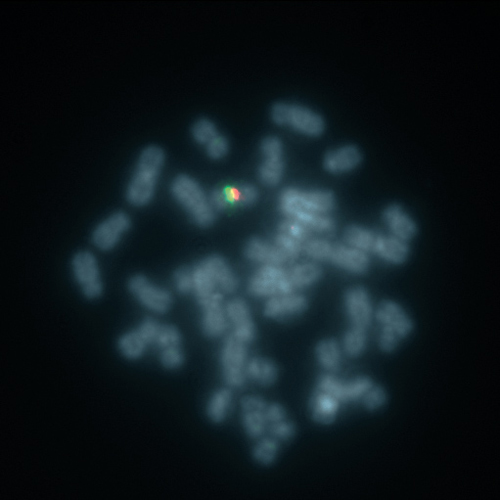

X-Inactivation XIST (Xq13) / SE X probe hybridized to a male metaphase (1R1G).

The XIST locus is expressed only from the inactive X chromosome, resides at the putative X inactivation center, and is considered a prime player in the initiation of mammalian X dosage compensation. The severe phenotype of human females whose karyotype includes tiny ring X chromosomes has been attributed to the inability of the small ring X chromosome to inactivate. Many of the ring chromosomes lack the XIST locus, consistent with XIST being necessary for cis inactivation. The XIST specific FISH probe is optimized to detect copy numbers of the XIST region at Xq13. The chromosome X Satellite Enumeration (SE X) FISH probe at DXZ1 is added to facilitate chromosome identification.